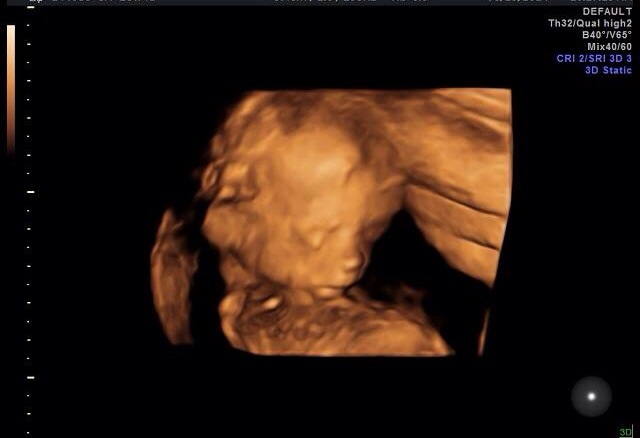

I have yet to really get a bump, wide hips and long torso. But I hope it's ok to share a pic from our A/S on Monday. It was a huge relief to get to see the little one happy and healthy! Also, the 3D/4D imaging is really cool, thankful that's what they use at my office!